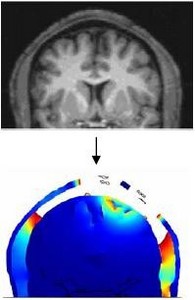

Deep Brain Stimulation (DBS) is a therapeutic tool used for a number of neurological disorders including chronic pain, incontinence and movement disorders, such as Parkinson’s disease. DBS consists of the low-frequency stimulation of an area of the brain, known as basal ganglia. ... Read More

To achieve a deeper understanding of the mechanism of the Deep Brain Stimulation (DBS) scientists use more and more numerical simulations. DBS inhibits overreaching brain activity via electric pulses that send into the brain by electrodes. Different electrode parameters such as geometry, ... Read More